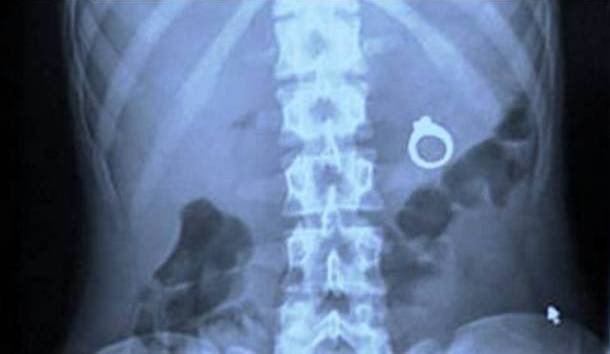

Khi một người đàn ông giấu tên đến từ New Mexico lên kế hoạch cầu hôn bạn gái mình, anh ta đã bí mật giấu chiếc nhẫn cưới vào món sữa lắc với ý định làm cô nàng ngạc nhiên bằng chiếc nhẫn đính kim cương nằm ở đáy cốc. Không may cho anh chàng ngớ ngẩn này, bạn gái của anh lại... đặc biệt khát vào ngày hôm đó và đã một hơi tu cạn cả sữa cả nhẫn.

Lẽ dĩ nhiên là lời cầu hôn này đã không được hoàn thiện cho tới tận thời điểm chiếc nhẫn "hoàn thành" chuyến đi của nó, tuy nhiên không có báo cáo nào ghi lại xem chiếc nhẫn này đã đi ra theo đường "tự nhiên" của cô gái hay phải có sự can thiệp của phẫu thuật.